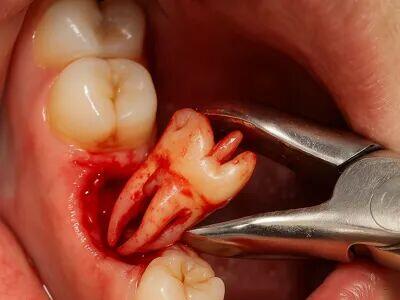

کاشت ایمپلنت دندان بدون درد و با ماندگاری بالا

ایمپلنت دندان؛ راهحلی علمی برای بازگرداندن لبخند